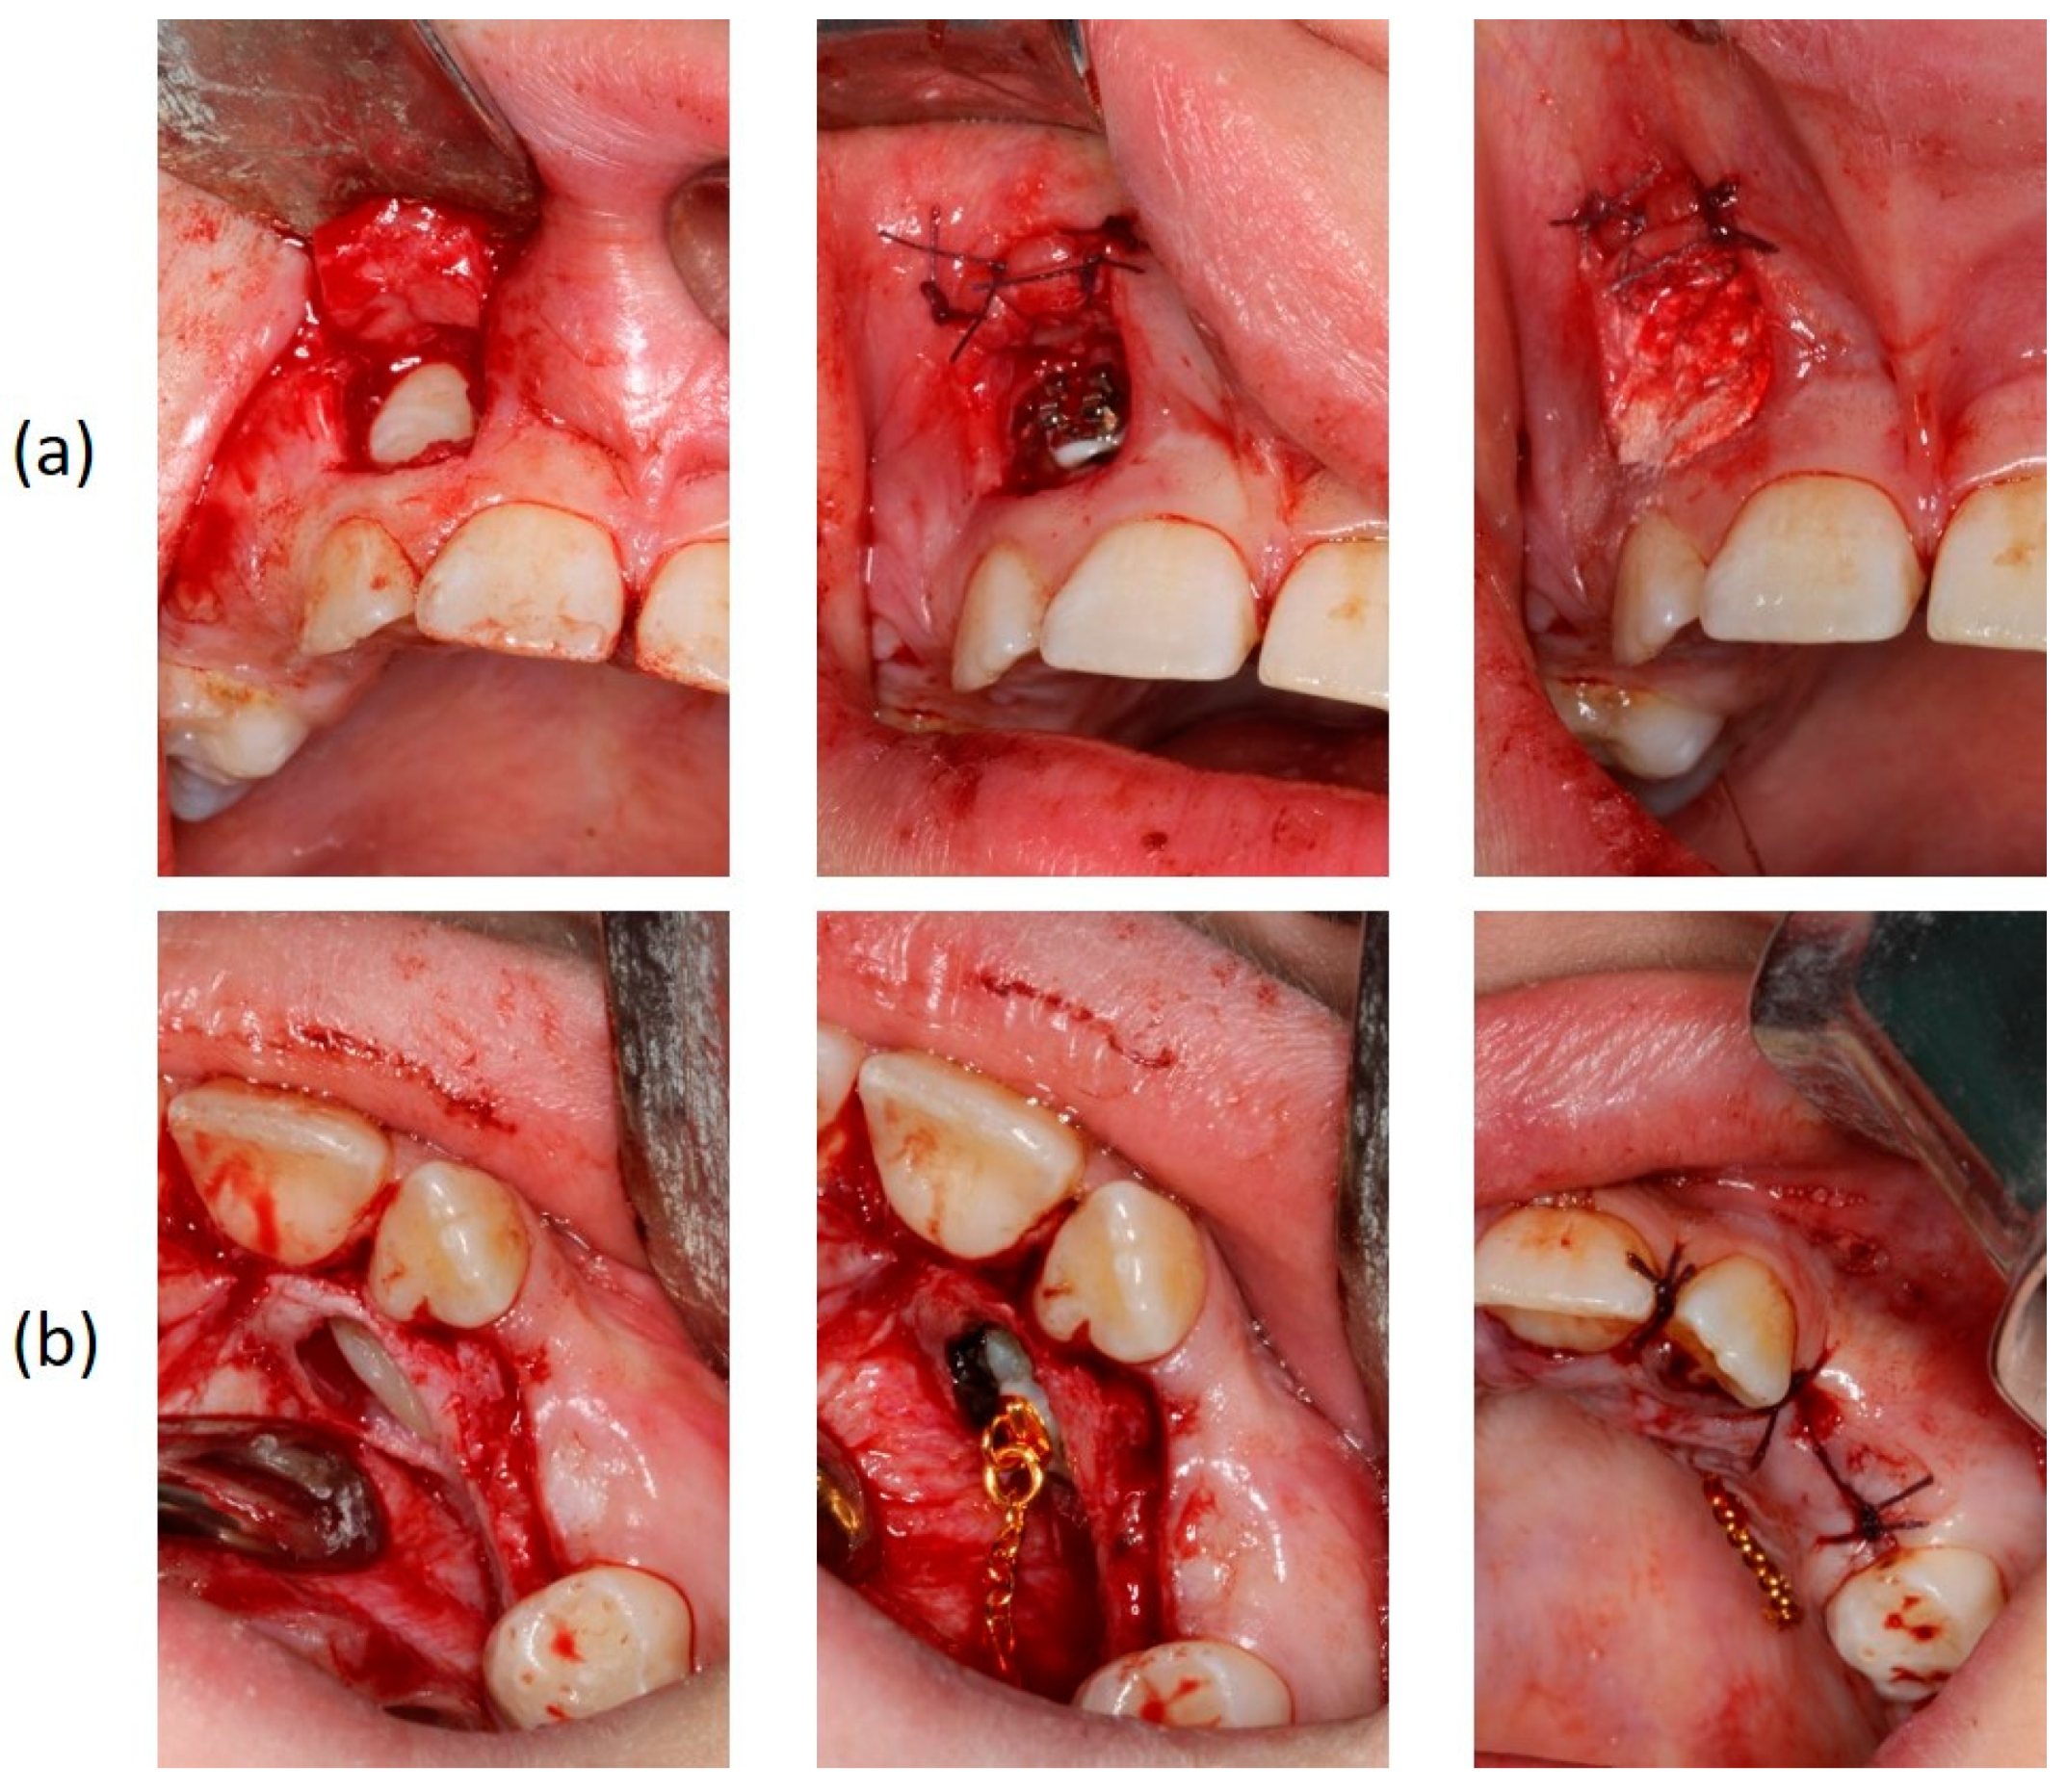

2.3. Treatment Planning

2.4. Treatment Results